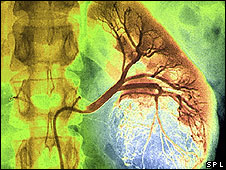

Cada año se hacen alrededor de 70.000 trasplantes de riñones en el mundo y se estima que entre 3.000 y 4.000 de esos órganos provienen del comercio de órganos, según cifras avaladas por la Organización Mundial de la Salud.